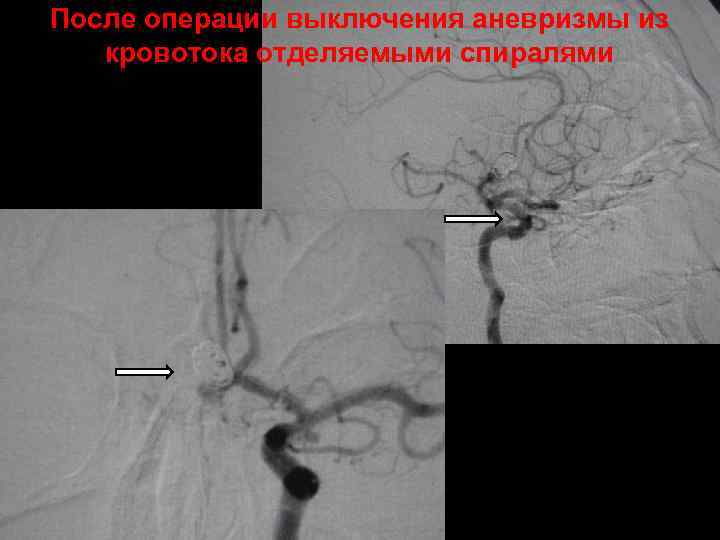

После операции выключения аневризмы из кровотока отделяемыми спиралями